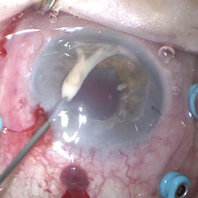

Removing a Hypopyon From the Anterior Segment

An intra-operative photograph demonstrating the technique of removing a hypopyon from the anterior segment.

Photographer: Philip Polkinghorne

Condition/keywords: endophthalmitis, fibrin, hypopyon